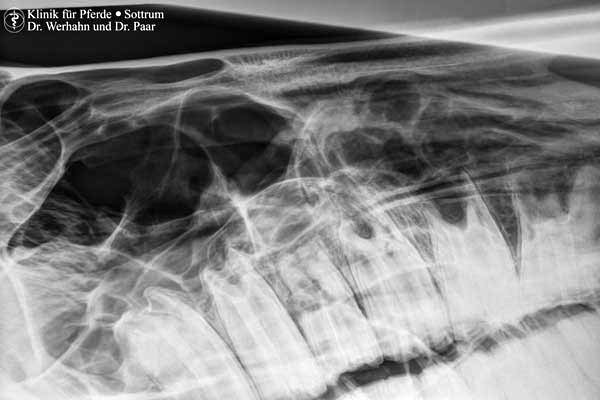

Neben den Standardaufnahmen im unteren Gliedmaßenabschnitt ist somit auch die röntgenologische Untersuchung von Ellbogengelenk, Schulter, Knie und Hüftgelenk, Halswirbelsäule, Rücken sowie von Kopf und Zähnen in sehr guter Qualität und unter Berücksichtigung der Anforderungen des Strahlenschutzes für die exponierten Personen möglich.

In der Inneren Medizin findet das Röntgen seinen Einsatz bei der Untersuchung des Kehlkopf und der Lunge, des Schlundes (Schluckstudien mit Kontrastmittel) und in der Kolikdiagnostik beim Fohlen und kleinen Pony.